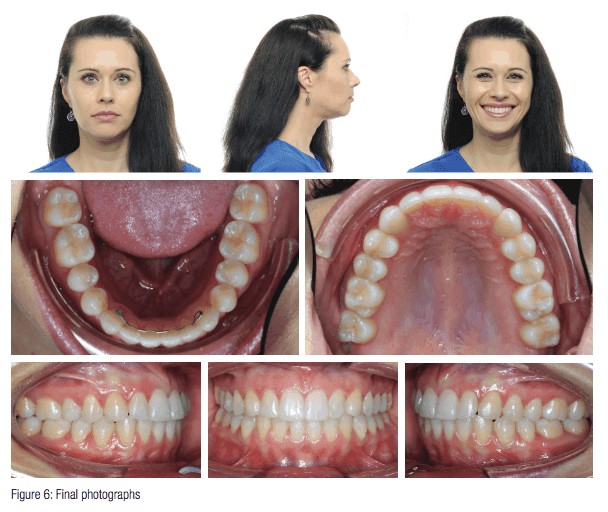

Figure 1 from Evaluation of Smile Line in Natural and Forced Smile …

Steps in Creating a Beautiful Smile | Aesthetic Advantage – Aesthetic …

Aesthetic dentistry expert – treatment of a gummy smile – Dentistry Online

What is the Gingival Smile Line? – West Palm Beach Dentist

Is A “Gummy Smile” Making You Self-Conscious?

Smile Gallery – Prettyman Orthodontics